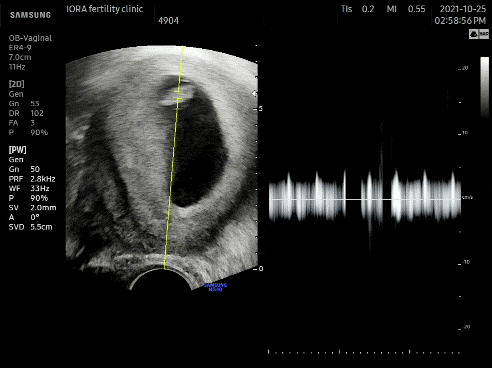

#심장음 #울롱삼 #초음파 전전주에 작은 심장음을 들었다면 7주차에는 큰 소리로 심장음을 들었다.콩알만 한데도 심장소리가 들리다니ㅠㅠ초음파를 볼 때마다 감동 아직 손발이 생기기 전이라 몸통과 머리만 있는 건장한 게 ㅎㅎ 2두신이다 귀여워 ㅎㅎ 의사선생님께서 아이는 7주차에 맞춰 잘 자라고 마음소리도 좋아서 다 좋다고 하셨다.입덧을 하며 “못 먹어도 너만 잘 컸으면 좋겠어”라고 건강에게 속삭였다. 건강하게 자라네아가ㅠㅠ!!

8주차 아이올라 방문! #초음파 몸통과 머리를 구별할 수 있는 튼튼함!흐흐흐 아 귀여워 너무 귀여워튼튼함이 잘 자라고 있구나! 훌륭하네!!점점 성장하는걸 초음파로 보면 나도 만족, 오빠도 만족. 이 순간만큼은 입덧도 감사(아이가 잘 자라고 있어서 입덧도 많이 나니까) 너만 잘 자라주면 뭐든지 좋아. 라는 생각으로 참는 것이,